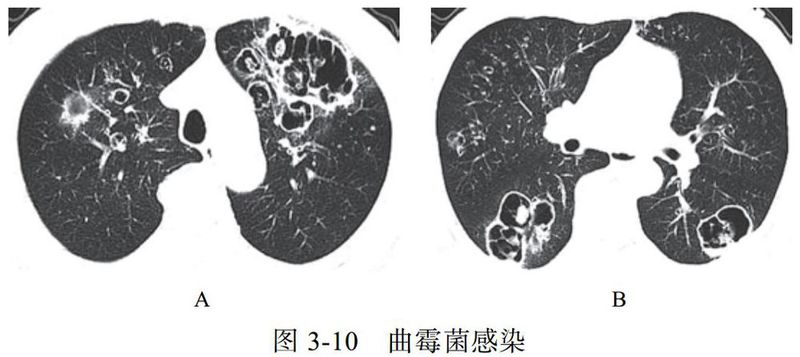

(一)曲霉菌感染

肺曲霉菌病主要是因吸入曲霉菌孢子而发病,是一种机遇性感染,为非化脓性炎症,可寄生于结核性空洞、肺癌空洞,以及慢性肺脓肿、肺囊肿、肺大疱及支气管扩张等病变所致的空洞或空腔内,少数因消化道或上呼吸道曲霉菌感染经血行播散至肺部。曲霉菌的菌丝呈游离状态,形成曲菌球。

影像学改变:

(1)典型征象为曲菌球(图 3-10)、空气半月征、手套征。

(2)多样化病灶并存,可伴有晕征、空洞、洞丝征及树上挂果征。

(3)曲菌球随体位改变而变化,球形内容物一般较光滑,密度均匀。